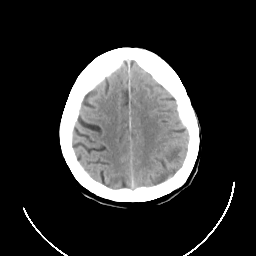

CT Study #3 -- Slice #22